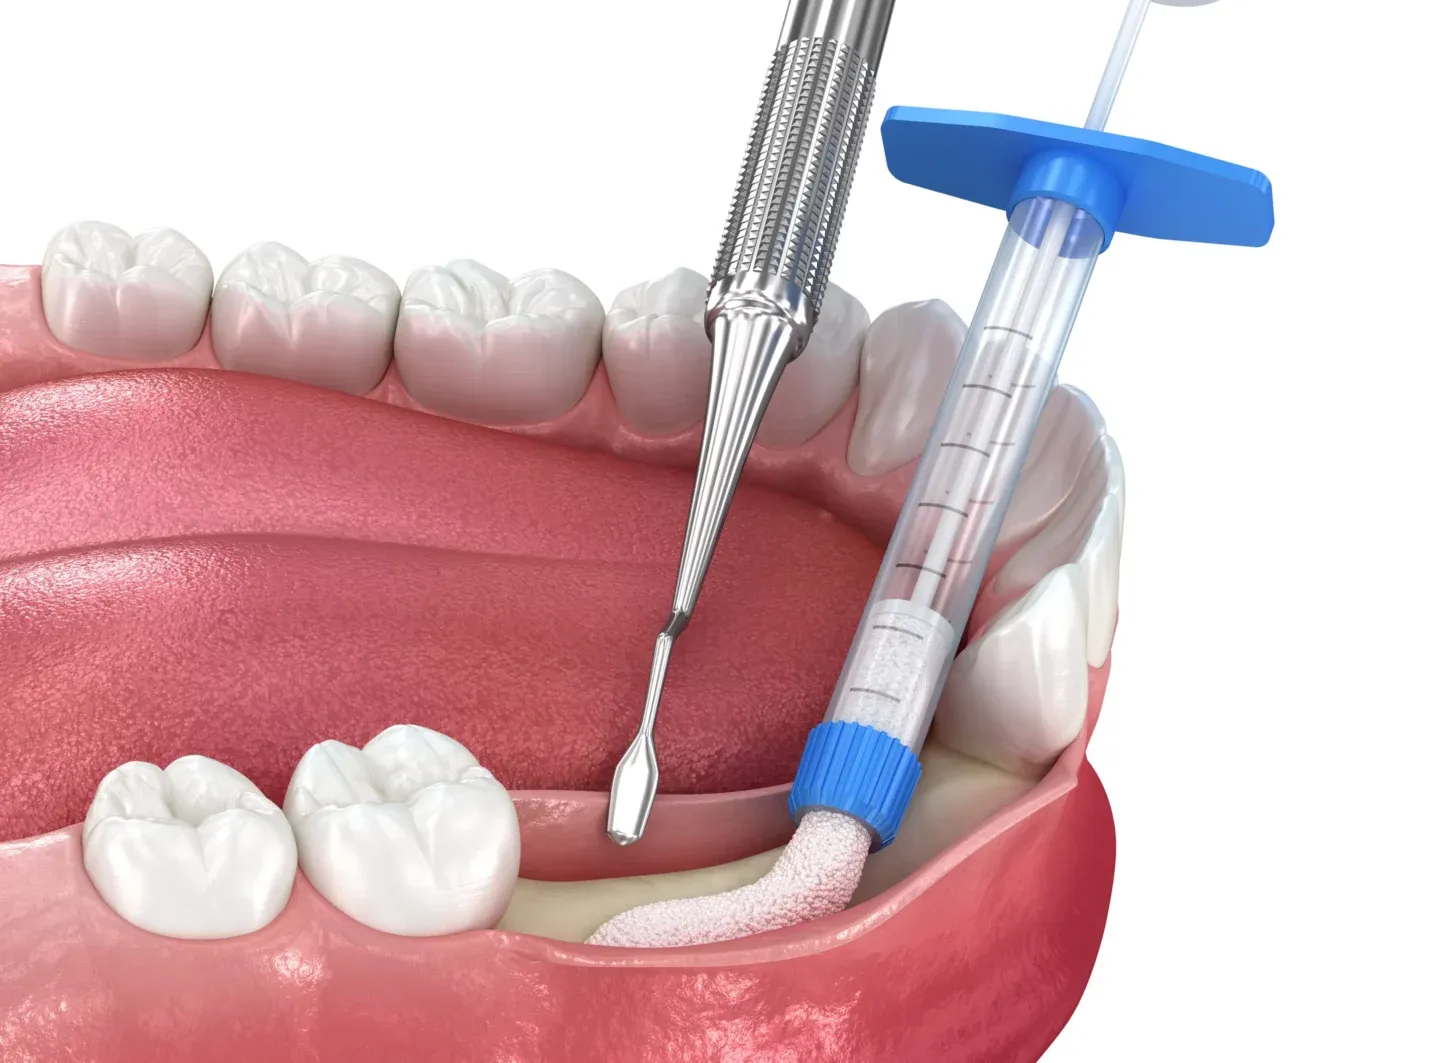

Коли йдеться про операцію по видаленню зубу мудрості, то це проводиться у кілька етапів:

- Спочатку хірургом виконується акуратний розріз ясен;

- Далі формується доступ у кістці до зубного кореня;

- Це поділяється за допомогою бормашини, витягується по одному;

- Отвір у кістці закривається;

- На ясна накладаються шви.